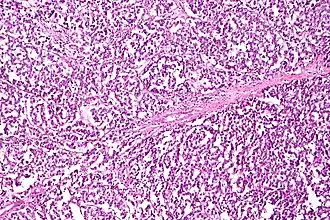

Micrograph of serous carcinoma, a type of ovarian cancer, diagnosed in peritoneal fluid

Diagnosis of ovarian cancer starts with a physical examination (including a pelvic examination), a blood test (for CA-125 and sometimes other markers), and transvaginal ultrasound.[26][58] Sometimes a rectovaginal examination is used to help plan a surgery.[29] The diagnosis must be confirmed with surgery to inspect the abdominal cavity, take biopsies (tissue samples for microscopic analysis), and look for cancer cells in the abdominal fluid. This helps to determine if an ovarian mass is benign or malignant.[26]